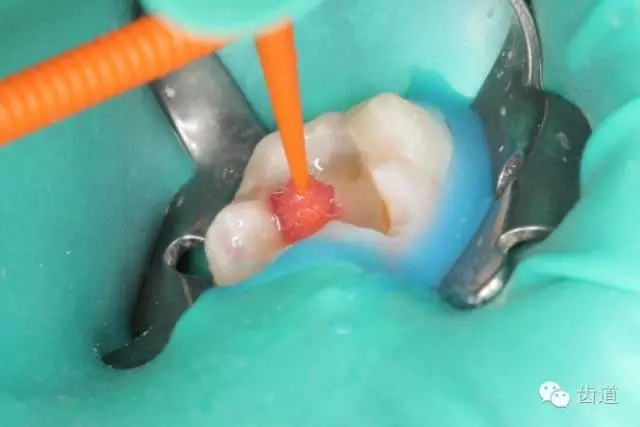

37無局部麻醉下,橡皮障放置,涂布邊緣封閉劑,顯微鏡下,合面開髓,死髓,無惡臭,無滲出液,Endo-Z開髓鉆揭全髓頂,探及髓腔內(nèi)壞死牙髓組織,3%次氯酸鈉浸泡髓腔5min,超聲清理髓腔,顯微鏡下探及近遠(yuǎn)中主根管,及根管間峽部。通過放入初尖銼及電子根管根管長度測量儀確定根管長度為18mm,利用手用K銼將根管預(yù)備至15#,再利用Waveone 25#預(yù)備根管至工作長度,之后,10ml 3%次氯酸鈉沖洗根管,超聲無菌水蕩洗,選取25#06錐度牙膠為主牙膠,拍攝示尖片,顯示到達(dá)根管長度。然后,17% EDTA凝膠處理根管壁,5ml 2%氯己定溶液完成終末沖洗,螺旋輸送器導(dǎo)入氫氧化鈣,放置棉球1,ZOE暫封。

4. 初步開髓

5. Endo-Z揭全髓室頂

6. 可見髓腔內(nèi)壞死牙髓組織,無滲出

7. 3%次氯酸鈉浸泡髓腔5min

8. 浸泡后超聲清理髓腔,去除髓腔內(nèi)殘留牙髓組織